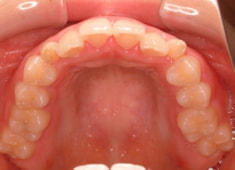

治療後(2年9ヶ月後)